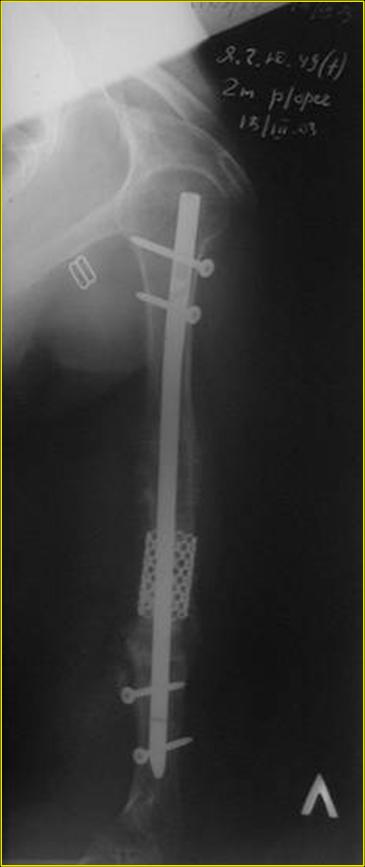

Типичная положительная ситуация для интрамедуллярного остеосинтеза с

использованием опорного металлокаркаса для компенсации дефекта.

Рентгеновская версия реконструкции. хронология:

после операции, 2 мес. после операции, через 1 год

Движения в полном объеме восстановлены к 2 мес. после операции. Если надо могу показать мультик. Сейчас уже прошло более 3 лет, больная не